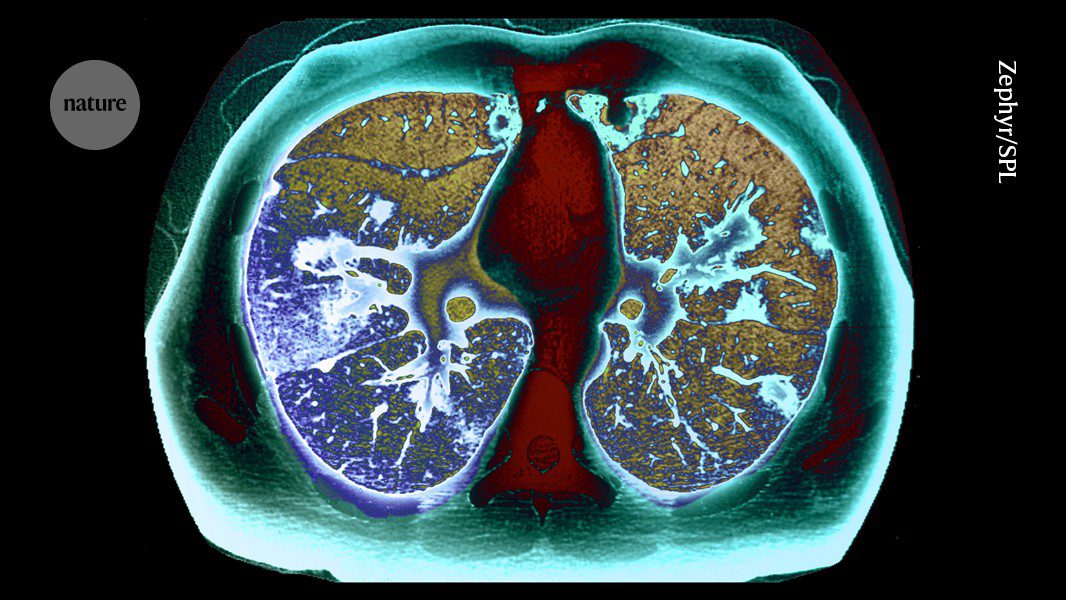

يقوم برنامج يقدم فحوصات للمدخنين الذين تتراوح أعمارهم بين 55 و74 عامًا بالكشف عن عدد كبير من أورام الرئة في المراحل المبكرة.